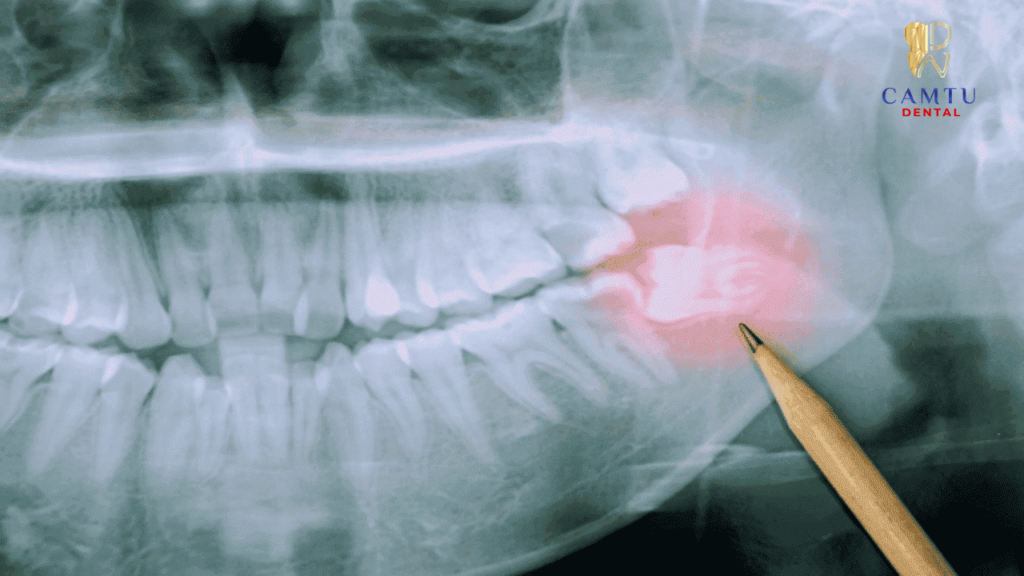

Thăm khám và chụp X quang răng

Bác sĩ tiến hành kiểm tra tổng quát tình trạng răng miệng nhằm xác định mức độ tổn thương của răng số 7. Sau đó, bệnh nhân sẽ được chỉ định chụp X quang để quan sát rõ cấu trúc chân răng, hướng mọc cũng như mối liên quan với các mô xung quanh.

Kết quả hình ảnh giúp bác sĩ đánh giá chính xác vị trí chân răng, độ cong hoặc số lượng chân răng, từ đó lên kế hoạch nhổ răng phù hợp và hạn chế tối đa rủi ro trong quá trình thực hiện.

Dựa trên kết quả thăm khám và phim X quang, bác sĩ sẽ phân tích mức độ viêm nhiễm, tổn thương của răng cũng như tình trạng xương ổ răng. Đồng thời, bác sĩ cũng kiểm tra tiền sử bệnh lý như tim mạch, tiểu đường hoặc rối loạn đông máu để đảm bảo việc nhổ răng diễn ra an toàn.